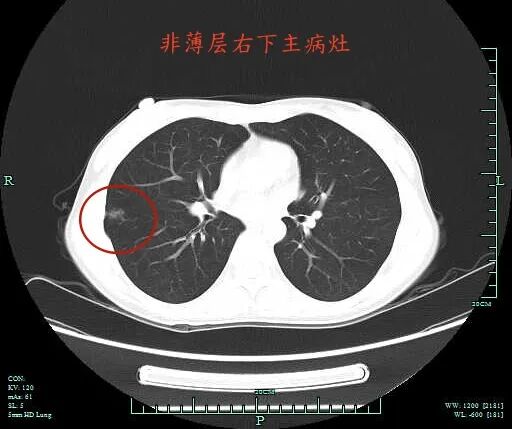

非薄层上右下主病灶A有微小血管进入,距离胸膜近,表面不平,灶内密度稍不均。